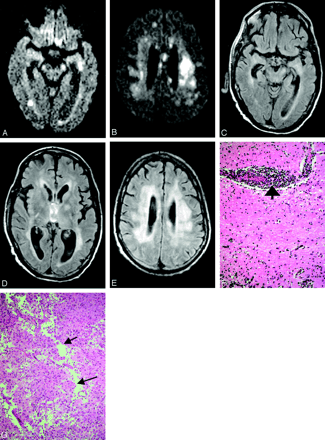

None of the brain parenchyma lesions was associated with enhancement. One MR imaging of the brain showed pachymeningeal enhancement; however, this patient had undergone lumbar puncture, so the enhancement could be reactive. There were 3 negative MR imaging spine studies of 6 reviewed, one of them unenhanced (Table 1). Two studies were positive for T2 hyperintensity in the cord, especially in the ventral horns along with nerve root enhancement (Fig 4A and -B). One study showed only nerve root enhancement.

Patient 16, an 80-year-old man presented with extremity weakness. Axial GRE image through cervical spine (A) shows increased signal intensity in the gray matter, whereas postcontrast sagittal T1-weighted sequences (B) reveal nerve root enhancement.

Midbrain involvement was noted in only 3 patients (Table 1); signal intensity abnormalities present in the cerebral peduncle and substantia nigra (Fig 2D, -J, and -K), as well as red nucleus (Fig 2N), are in accordance with prior case reports on Japanese and St. Louis encephalitides (13, 15). Involvements of the pontine tegmentum (Fig 1A and -B) and superior cerebellar peduncles (Fig 1C) were the first abnormalities to be noticed in one of the patients (2), who became ventilator dependent and progressed to develop flaccid paralysis. There were 4 patients who presented at some point with extremity weakness. All, with one exception (17), had MR imaging studies of the spine; abnormalities were seen in the gray matter and particularly the ventral horns in 2 of them, whereas enhancement of the conus medullaris and the cauda equina was seen in all 3. Prior reports have associated the flaccid paralysis with enhancement around the conus and along the cauda equina (2, 3). Anterior myelitis apparently contributes to the clinical picture as well (Figs 1E–G and 4A and -B). Abnormalities in the dentate nuclei, cerebellar white matter, and cortex were present in only one patient (Fig 2F, -G, -L, and -M) and are depicted on one of the follow-up MR imaging studies coinciding with newly developed “polio-like” symptoms. Unfortunately the patient’s spine was never imaged, so whether there were any additional findings of anterior myelitis and/or radiculitis remains unknown.